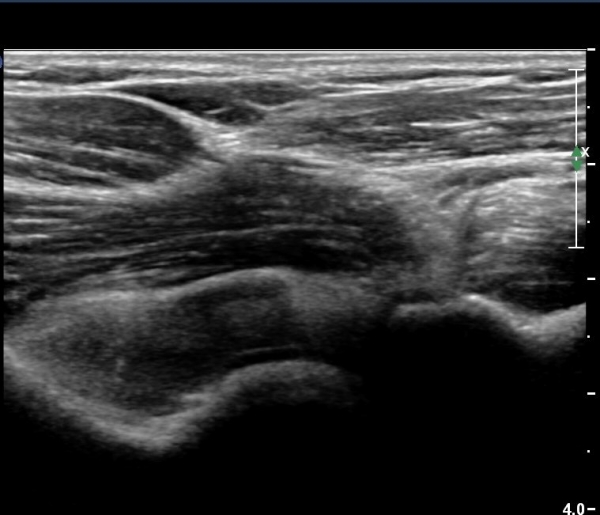

ÁÖµÎ¿Í Á¾´Ü¸é°Ë»ç¿Í Ⱦ´Ü¸é°Ë»ç¿¡¼­ ÁֵοͿ¡ ÀÌÁúÀû¿¡ÄÚ¸¦ º¸ÀÌ´Â

´Ù·®ÀÇ ¼ö¾×Àú·ù°¡ °üÂûµÊ(»çÁø 5, 6).

ÃÊÀ½ÆÄ°Ë»ç¿¡¼­ ÀÌÁúÀûÀÎ °í¿¡ÄÚ ¼ö¾×Àú·ù´Â ÀüÇüÀûÀÎ ±Þ¼º °üÀý³» ÃâÇ÷ ¼Ò°ßÀÌ´Ù.

ÀÌ·± ¼Ò°ßÀ» º¸ÀÌ´Â °æ¿ì¿¡´Â °üÀý³» °ñÀýÀ» ÀǽÉÇÏ°í °ñÀý È£¹ß ºÎÀ§¸¦ ¼¼½ÉÇÏ°Ô °Ë»çÇØ¾ß